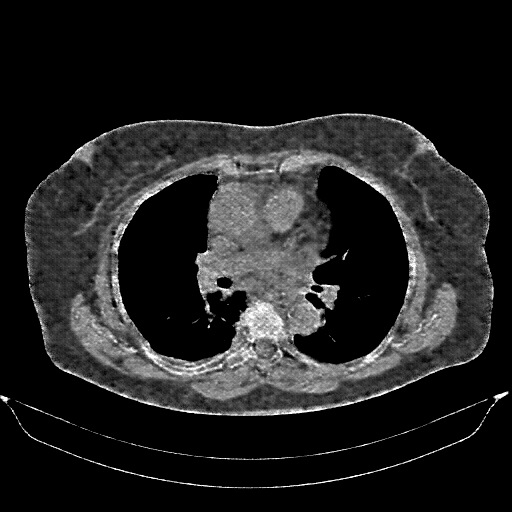

Targeted Slice 70 - Mediastinum Window Analysis (Generated vs Real Venous)

0.655

Mediastinum SSIM

46.3

Mediastinum RMSE

19.4

Mediastinum MAE

Average Mediastinum Window Metrics Across All Slices (161 slices) - Generated vs Real Venous

0.648

Mediastinum SSIM (Avg)

47.9

Mediastinum RMSE (Avg)

20.7

Mediastinum MAE (Avg)

Generated VENOUS CT scan (A→B translation)

No window - Raw intensity values

Lung window (WL -600, WW 1500 β†’ Low βˆ’1350, High +150)

Mediastinum window (WL 40, WW 400 β†’ Low βˆ’160, High +240)